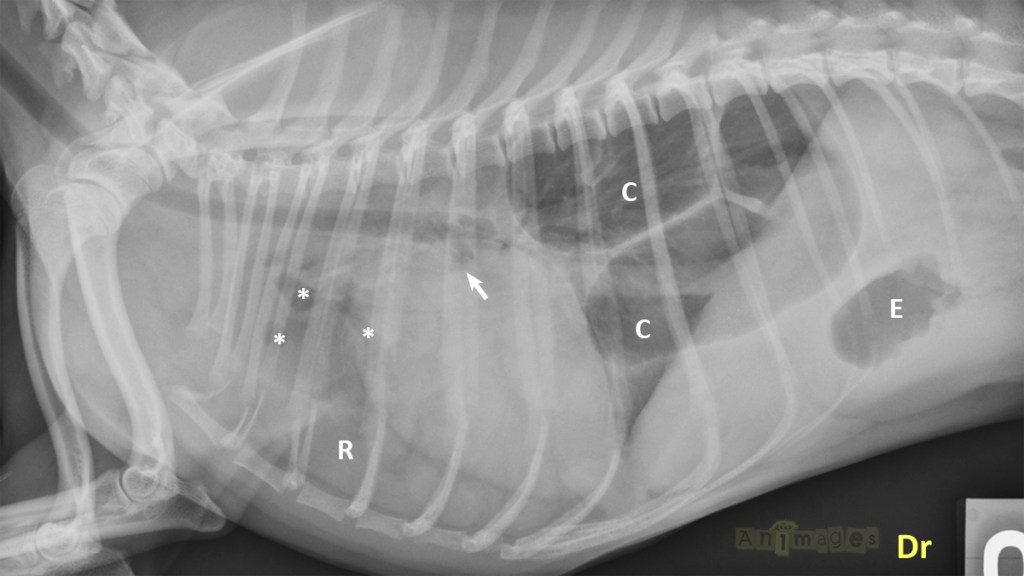

lat-annot